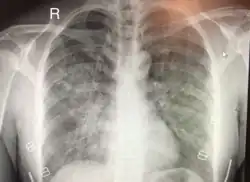

Chest x-ray of HAPE showing characteristic patchy alveolar infiltrates with right middle lobe predominance.

Hypoxic pulmonary vasoconstriction (HPV) occurs diffusely, leading to arterial vasoconstriction in all areas of the lung. This is evidenced by the appearance of "diffuse," "fluffy," and "patchy" infiltrates described on imaging studies of climbers with known HAPE.[9]

On physical exam, increased breathing rates, increased heart rates, and a low-grade fever 38.5o C (101.3o F) are common.[9][3] Listening to the lungs may reveal crackles in one or both lungs, often starting in the right middle lobe.[9][3] Imaging studies such as X-ray and CT imaging of the chest may reveal thoracic infiltrates that can be seen as opaque patches.[14][9][3] One distinct feature of HAPE is that pulse oximetry saturation levels (SpO2) are often decreased from what would be expected for the altitude. People typically do not appear as ill as SpO2 and chest X-ray films would suggest.[9][3] Giving extra oxygen rapidly improves symptoms and SpO2 values; in the setting of infiltrative changes on chest X-ray, this is nearly pathognomonic for HAPE.[3]